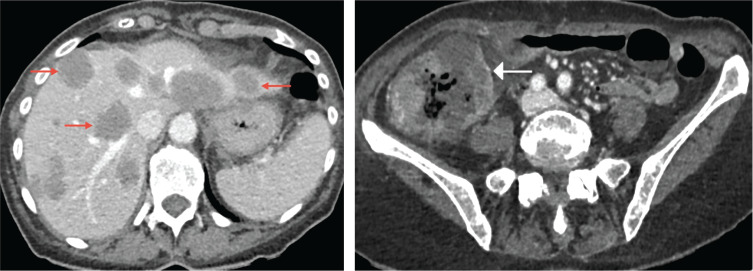

A rare case of hepatic gas-forming metastases secondary to Clostridium septicum infection is described. A 78-year-old woman was admitted with right lower quadrant abdominal pain and deterioration. Initial imaging revealed a right-sided colonic malignancy with hepatic metastases. Follow-up scans showed gas within metastases and minimal pneumoperitoneum, suggesting bowel perforation. However, blood cultures isolated C. septicum, supporting infected necrotic metastases as the source of free gas. Teaching point: This case emphasizes the importance of distinguishing infectious intratumoral gas from perforation in oncological patients and provides one of the few reports with sequential imaging of this process.